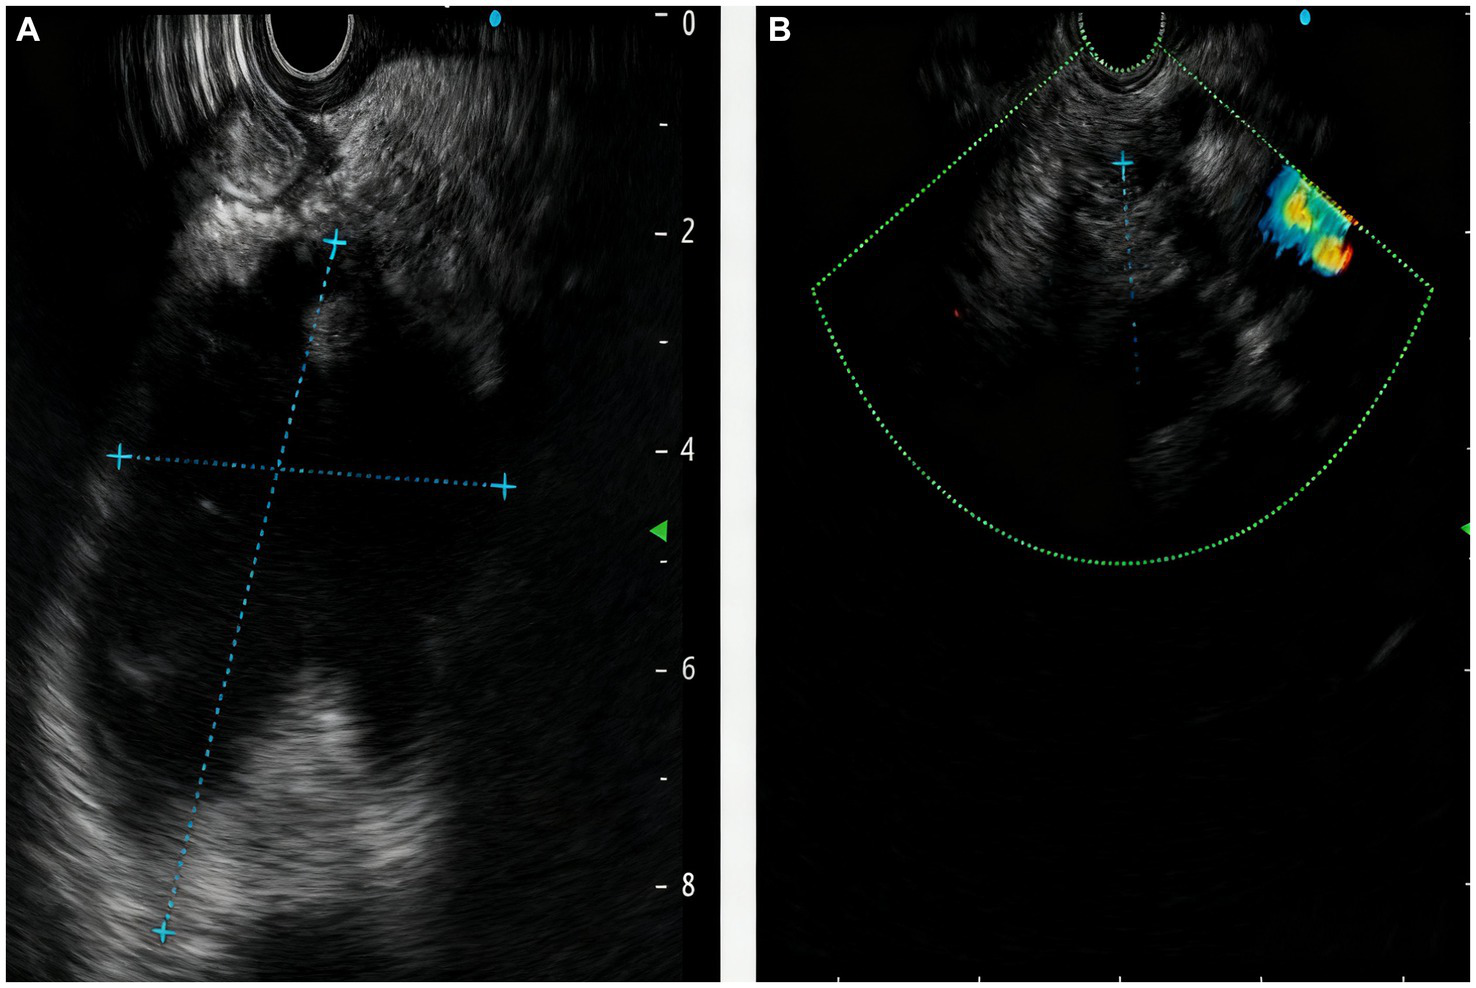

A 64-year-old male of Asian with a documented history of acute pancreatitis 11 months prior presented with recurrent severe epigastric pain, a CT scan that revealed pancreatic enlargement with ill-defined margins and heterogeneous density, along with a cystic hypodense lesion measuring approximately 5.9 cm × 4.9 cm × 7.7 cm posterior to the pancreatic head. This lesion showed slightly thickened walls without mural nodules, had an indistinct border with the pancreatic head, and was accompanied by pancreatic duct dilation at 9 mm and ill-defined fat planes surrounding both the pancreas and duodenum (Figure 1A). The endoscopic ultrasonography demonstrated that a cystic lesion was identified in the head and neck of the pancreas measured approximately 6.7 cm × 5.4 cm in its largest cross-sectional dimension, without definite mural nodule. The main pancreatic duct (MPD) distal to the cyst is dilated, measuring up to 0.7 cm in diameter, and communicated with the cyst (Figure 2A). Upon initial evaluation, he was noted to be underweight with a body-mass index (BMI) of 16.29 kg/m2. Laboratory results showed increased amylase of 175 U/L, lipase of 76 U/L, and alpha-fetoprotein (AFP) of 14.3 ng/mL. Carcinoembryonic antigen (CEA), CA 19–9, total bilirubin, alanine aminotransferase (ALT) and aspartate aminotransferase (AST) were all within normal limits.

Figure 2

The manifestations of the pancreas under endoscopic ultrasound revealed the (A) a cystic lesion measured approximately 6.7cm x 5.4cm in its largest cross-sectional dimension, communicated with the MPD; (B) reduction in the size of pancreatic cystic lesion after 2 months.

After two-month follow-up, we removed the pancreatic duct stent (Figure 4). His BMI had improved at 17.56 kg/m2, findings compatible with clinical improvement. Imaging studies both in CT scan and endoscopic ultrasonography confirmed reduction in the size of his PPC (measuring 2.2 cm × 0.8 cm × 1.1 cm) and his previously mentioned elevated laboratory values were all within normal limits (Figures 1B, 2B).